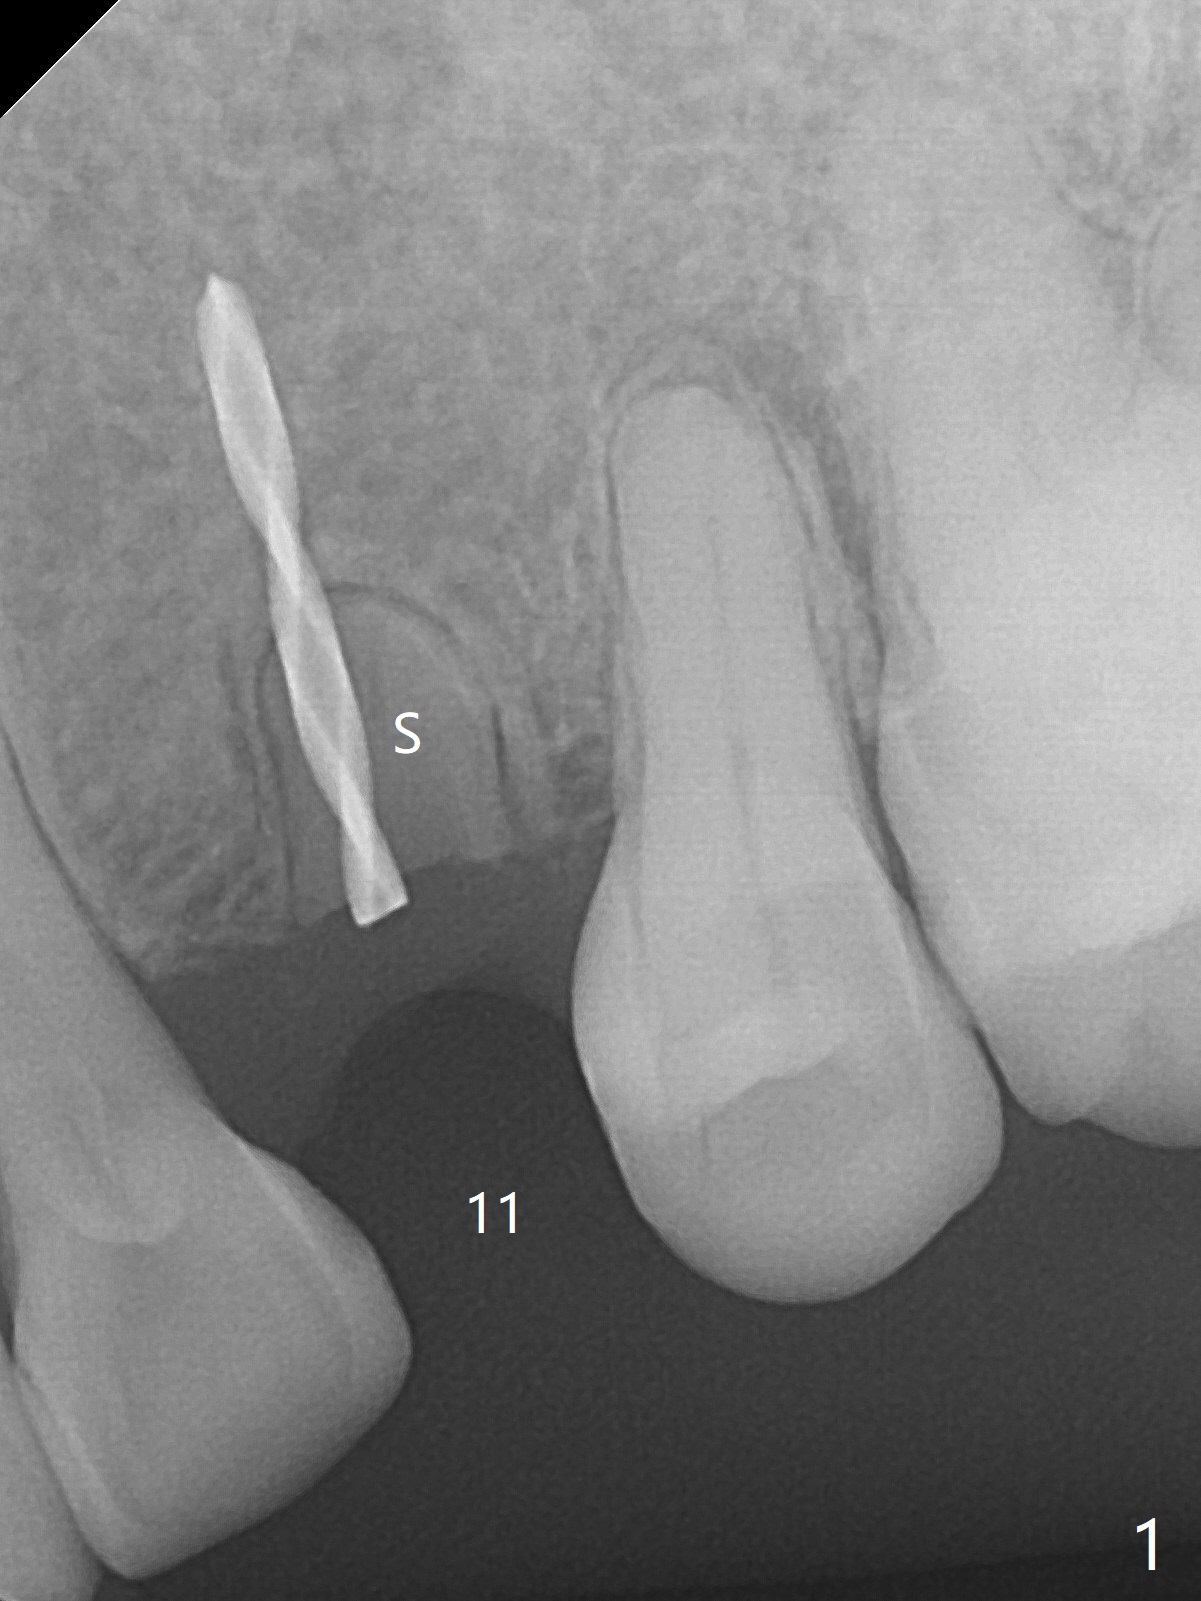

At surgery, the mesiodistal space for #11 is found to be narrow, 5 mm. To prevent buccal plate collapse, socket shield is planned. Due to limited space, incision is attempted so that the lower end of the shield (Fig.1 S) can be trimmed slightly subcrestal. It is also good for visibility for osteotomy (1.2 mm drill for 12 mm). A 2.5x14(2) mm 1-piece implant is placed with <35 Ncm (Fig.2,3 (*: allograft)). An immediate provisional is fabricated to the patient's satisfaction. There is no bone loss 3.5 months postop (Fig.4) or 4 months postop (Fig.5 *, corresponding to S in Fig.3). The recessive papillae are expected to reform to certain degree due to limited damage to the crestal bone.